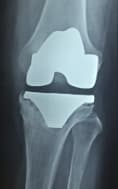

А. Мэс засал хийсэн өвдөгний үе

Б. Бүтэн биеийн рентген зураг

Зураг 2. Мэс заслын дараах рентген зураг